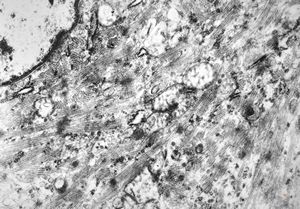

M,56y. | amyloidosis - tendon